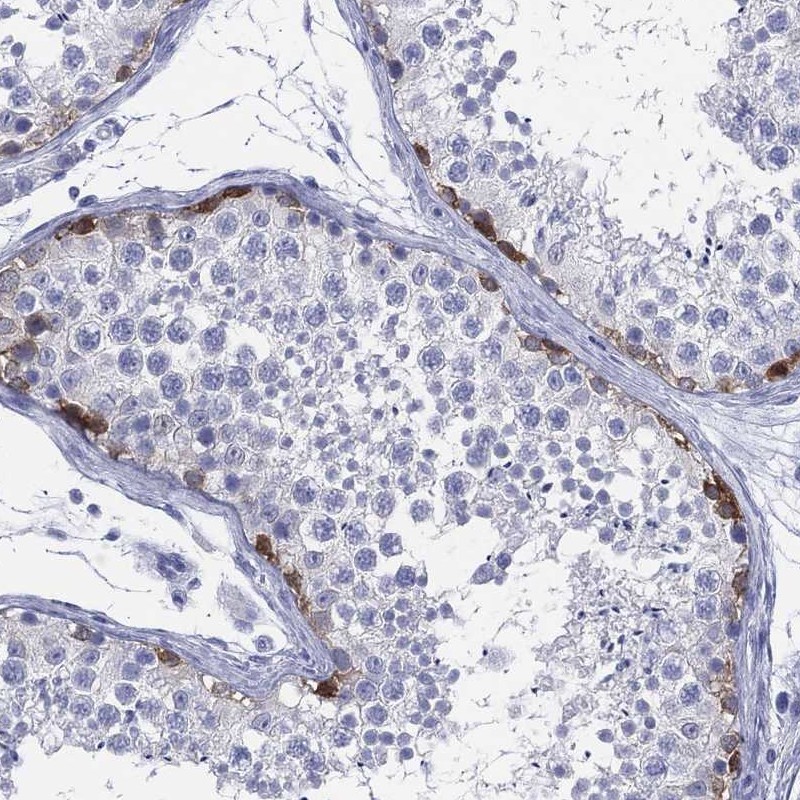

Immunohistochemistry analysis in human testis and rectum tissues using Anti-LRRD1 antibody. Corresponding LRRD1 RNA-seq data are presented for the same tissues.